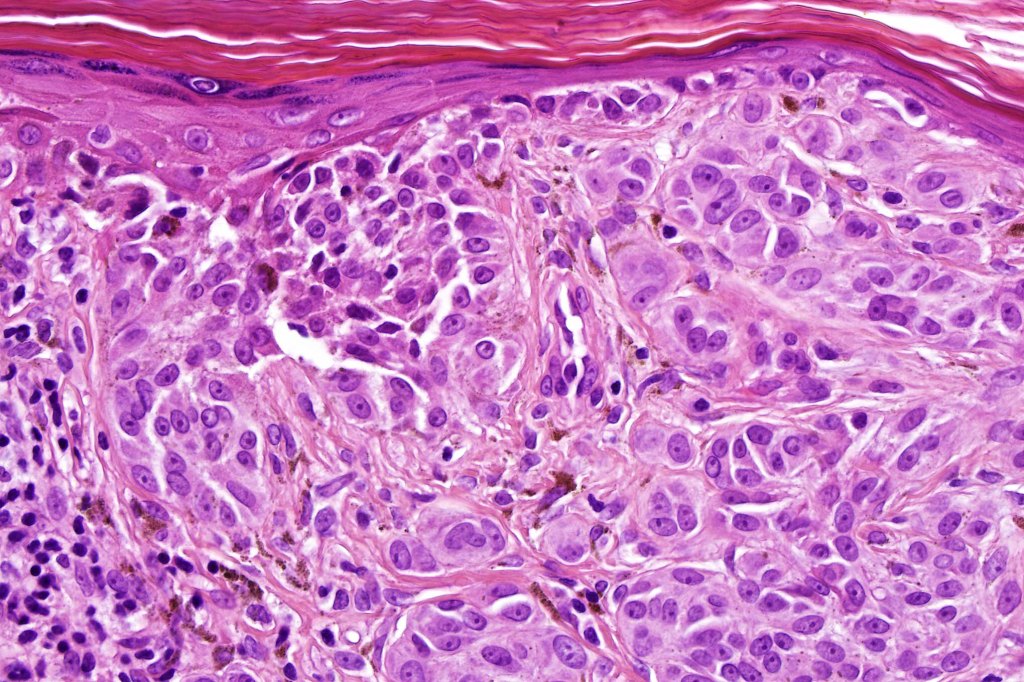

Combined Spitz & common blue nevus